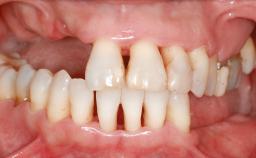

A 47-year-old Caucasian woman with a single-tooth edentulous space at the site of the left maxillary canine was referred for treatment. She had undergone traumatic extraction of this impacted canine several months before referral. Her chief complaint was the dissatisfying appearance of her smile. The patient desired a stable and esthetic rehabilitation of the site. Her dental history showed no evidence of periodontal disease or bruxism. She had no systemic diseases, was not taking any medications, and did not smoke. The extraoral examination revealed a high lip line and an inadequate soft-tissue volume at the defective canine site. Large black triangles were visible between the canine and its adjacent teeth.

Lip Line No exposure of papillae Exposure of papillae Full exposure of mucosa margin

Periodontal Phenotype Low-scalloped, thick Medium-scalloped, medium-thick High-scalloped, thin

Soft Tissue Anatomy Intact Defective